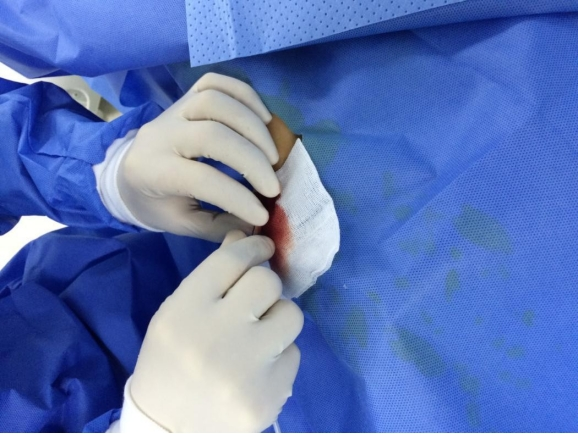

置鞘:

右手稳住针鞘,左手缓慢退出穿刺针;待针鞘向外喷血,左手稳住针鞘,右手持导丝从尾部放入针鞘,直至2/3进入体内;左手按住穿刺点,右手捏住针鞘缓慢退出体内,保留导丝;用扩皮刀在穿刺点口轻轻向上挑开皮肤完成扩皮;右手持肝素盐水冲洗过的已组装好的桡动脉鞘管,通过导丝并在左右旋转下进入桡动脉,直至合适长度;左手稳住桡动脉鞘管,右手将导丝连同鞘芯一起退出体外。

两点法:两个桡A搏动点以明确血管走行;穿刺点:桡骨茎突近心端水平;角度:30度左右;穿刺法:穿透法比喷血法好;少用局麻:皮下,少于0.5ml利多;预防痉挛:硝酸甘油200μg鞘内注射;穿透法喷血后左手扶针鞘,缓慢退鞘,手一定要稳;导丝进入困难时建议导丝塑弯透视下调整。